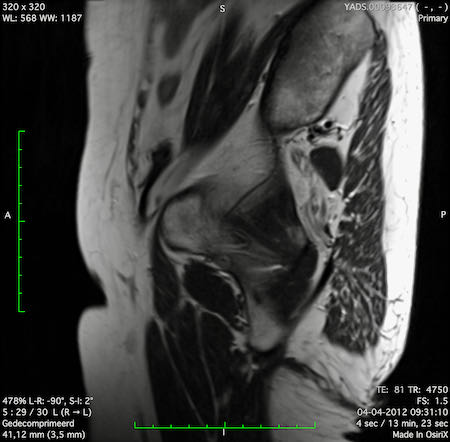

Hình ảnh

Các hình ảnh được cung cấp cho thấy ung thư biểu mô tế bào nhẫn với tình trạng dày lan tỏa thành trực tràng, hình ảnh bia bắn điển hình, và sự xâm lấn mỡ mạc treo trực tràng.